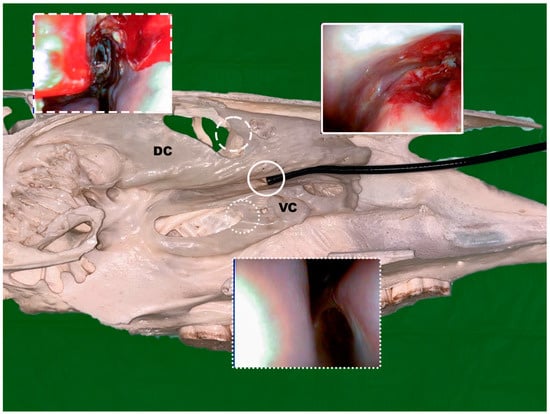

2.2.4. Endoscopic Guided Conchotomy

2.2.5. Transendoscopic Laser Fenestration of the Nasal Conchae

2.2.6. Transendoscopic Fenestration of the Bulla of the Maxillary Septum (BMS)